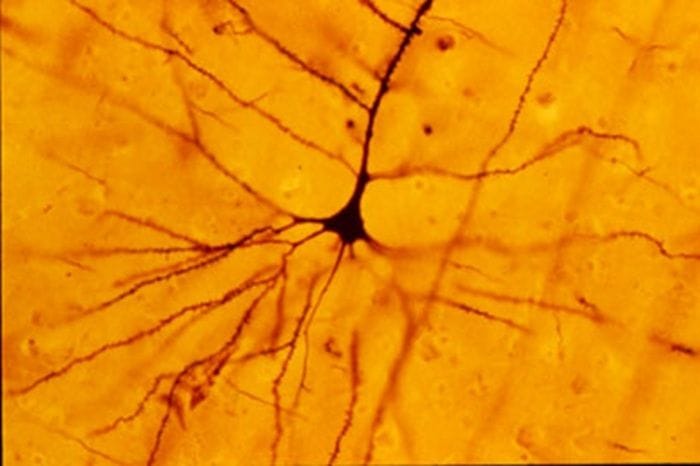

Dalla scoperta dei cosiddetti

neuroni specchio

, che si attivano sia quando compiamo un'azione sia quando la osserviamo fare a qualcun altro, agli studi che hanno fatto luce sulla

reazione nera

': la tecnica di colorazione da lui sviluppata nel

1873

, che permise per la

prima volta

di evidenziare e

osservare

le singole

cellule cerebrali

.